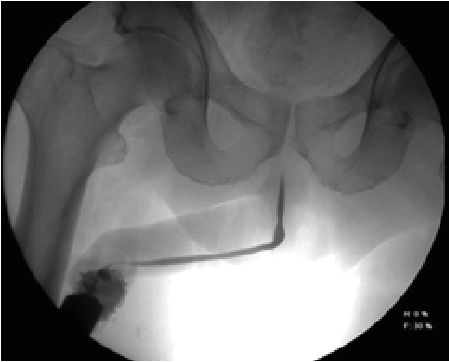

The identification of the anatomical portions of the urethra by retrograde urethrography is part of the learning process of the radiologist technician and medical resident in radiology, which seems easy and yet they are part of daily errors (Figure 4,5,6), it consists the penile urethra, bulbar, bulbomembranous, membranous, urogenital diaphragm, prostatic and verumontanum [2].

Figure 6: 63-Year-Old Male with a History of Prostatic Tran’s Urethral Resection, Which Presented Difficulty in Urination, Was Diagnosed by Image as Posterior Bulbar Stenosis and by Cystoscopy was Anterior Bulbar Urethral Stenosis